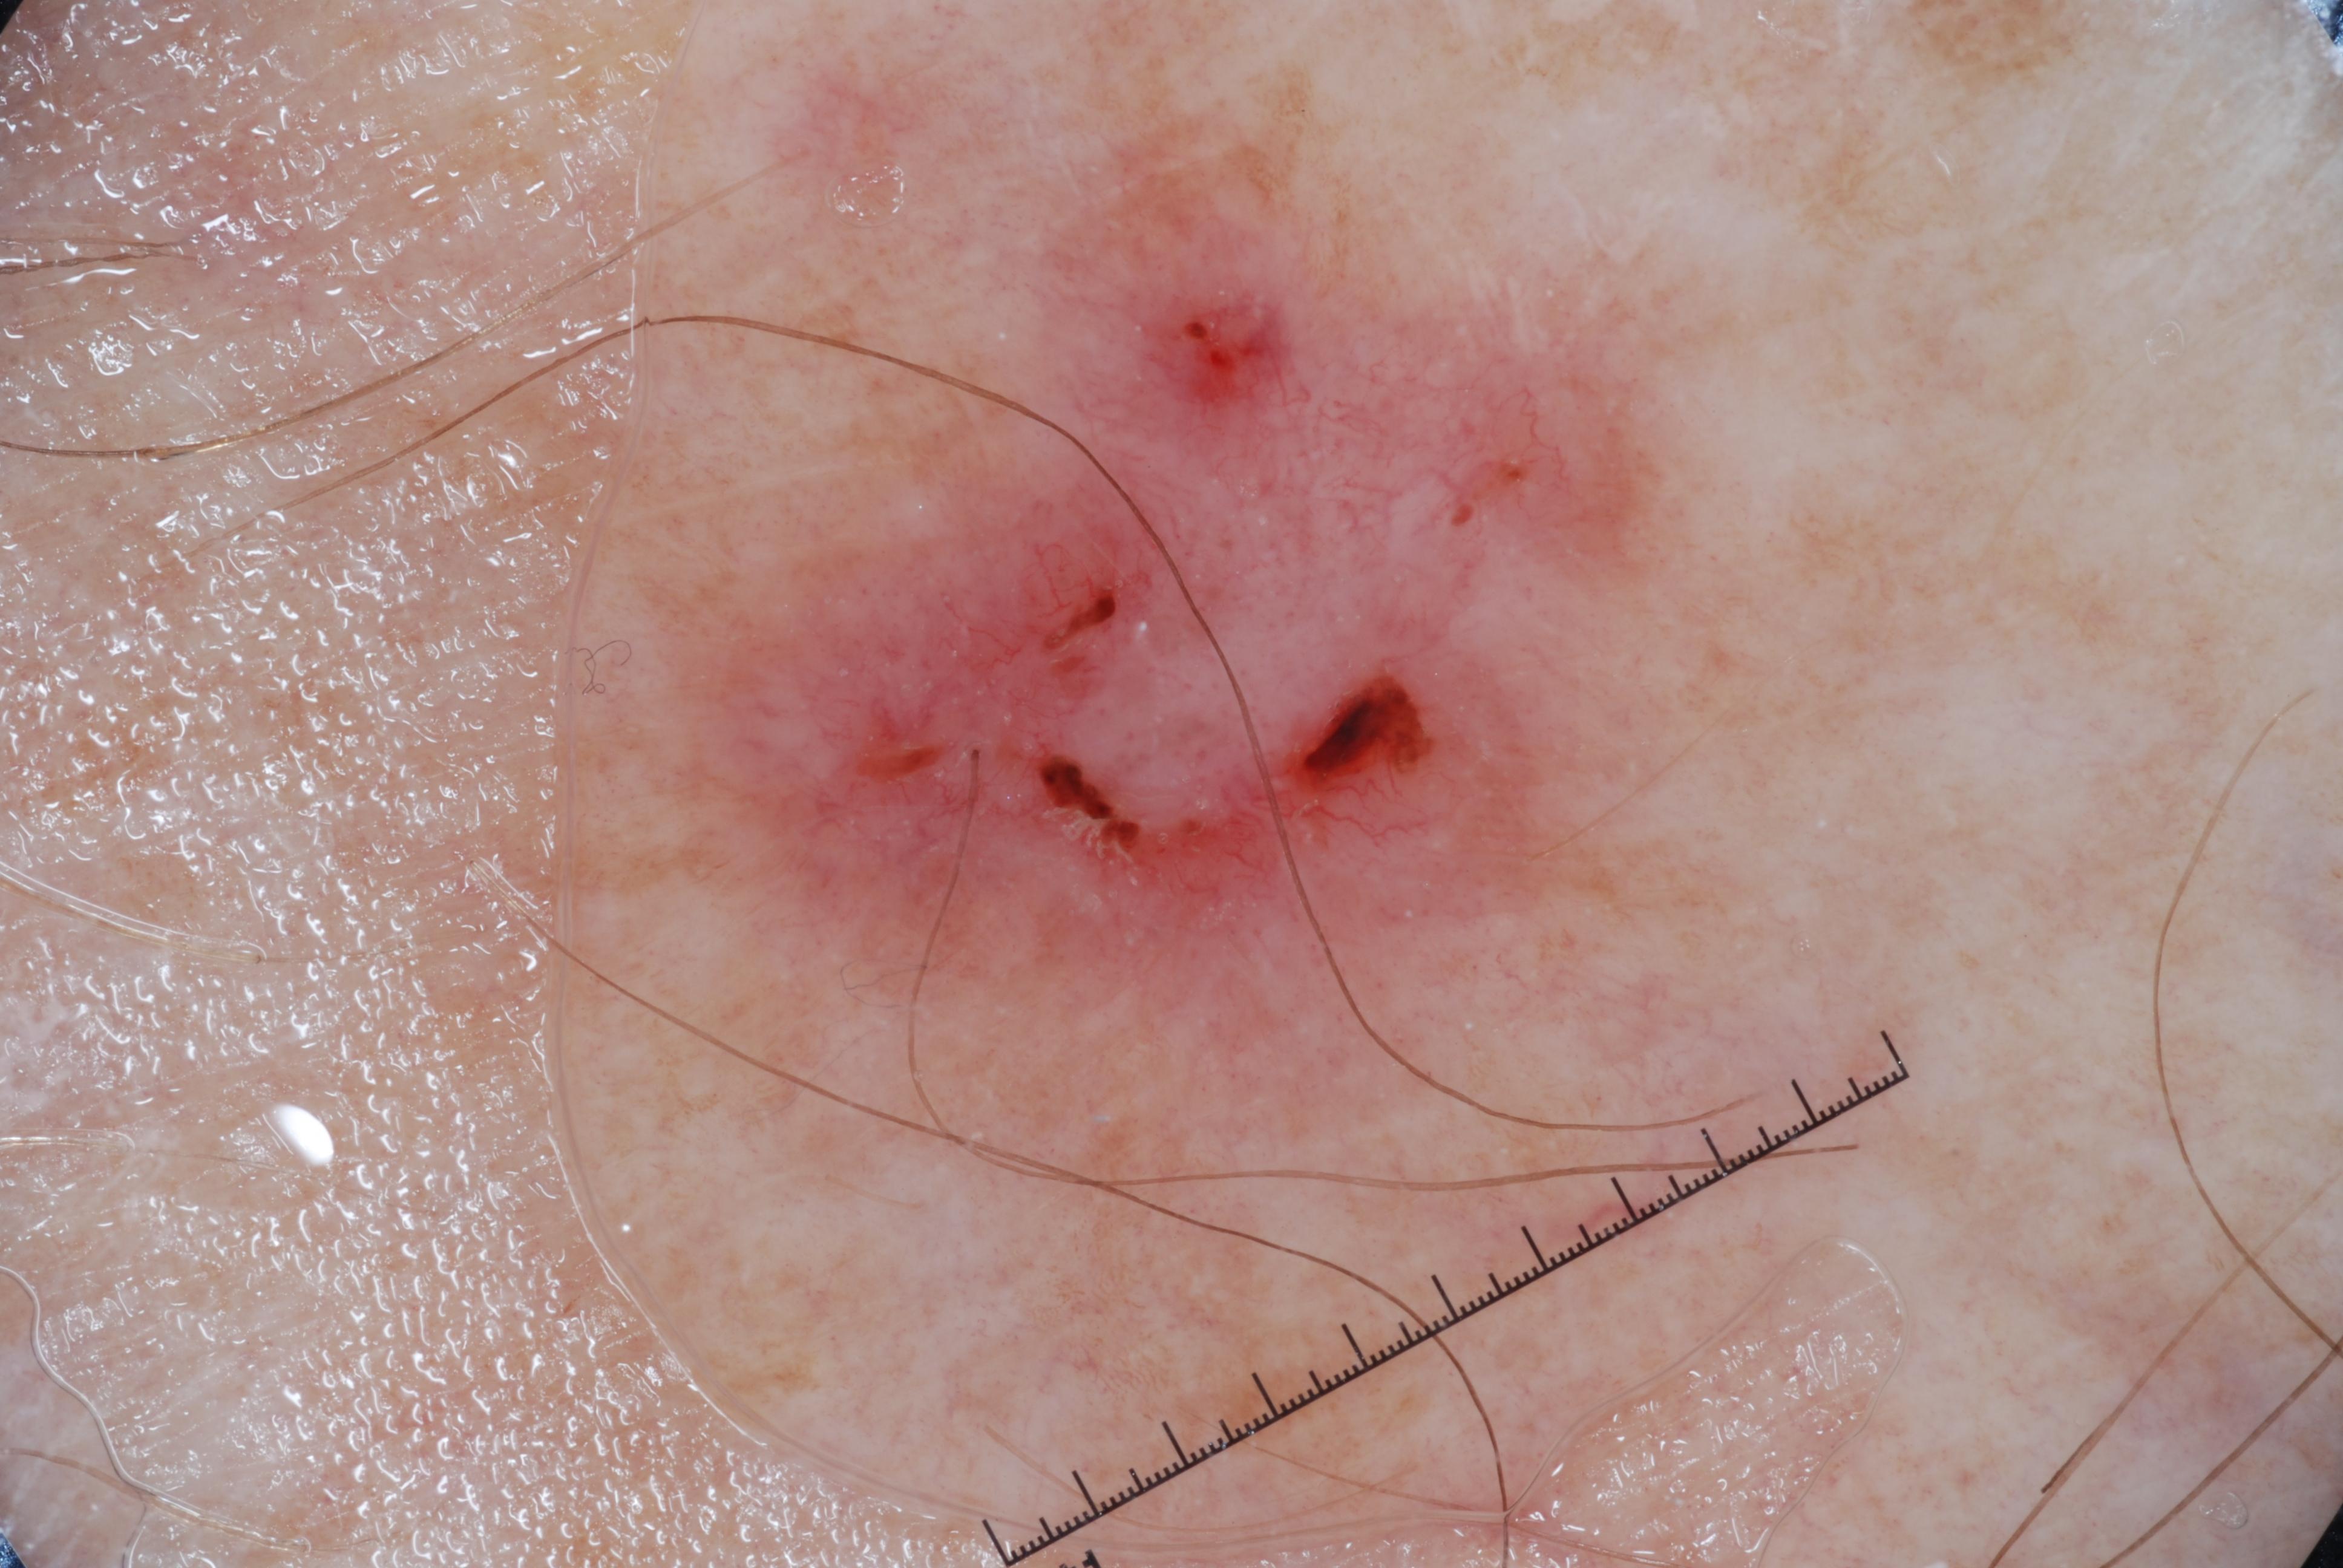

{

"age_approx": 85,

"anatom_site_general": "upper extremity",

"concomitant_biopsy": true,

"dermoscopic_type": "contact non-polarized",

"diagnosis_1": "Malignant",

"diagnosis_2": "Malignant epidermal proliferations",

"diagnosis_3": "Squamous cell carcinoma, NOS",

"diagnosis_confirm_type": "histopathology",

"image_type": "dermoscopic",

"lesion_id": "IL_7567412",

"melanocytic": false,

"sex": "female"